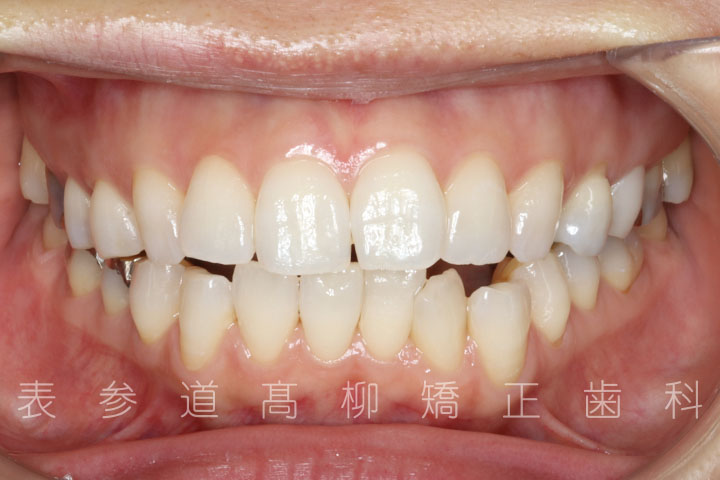

上下4本第二小臼歯抜歯症例

口呼吸と舌癖で前歯が咬み合わない患者様の症例をご紹介いたします。

治療前→治療後

術前術後の比較